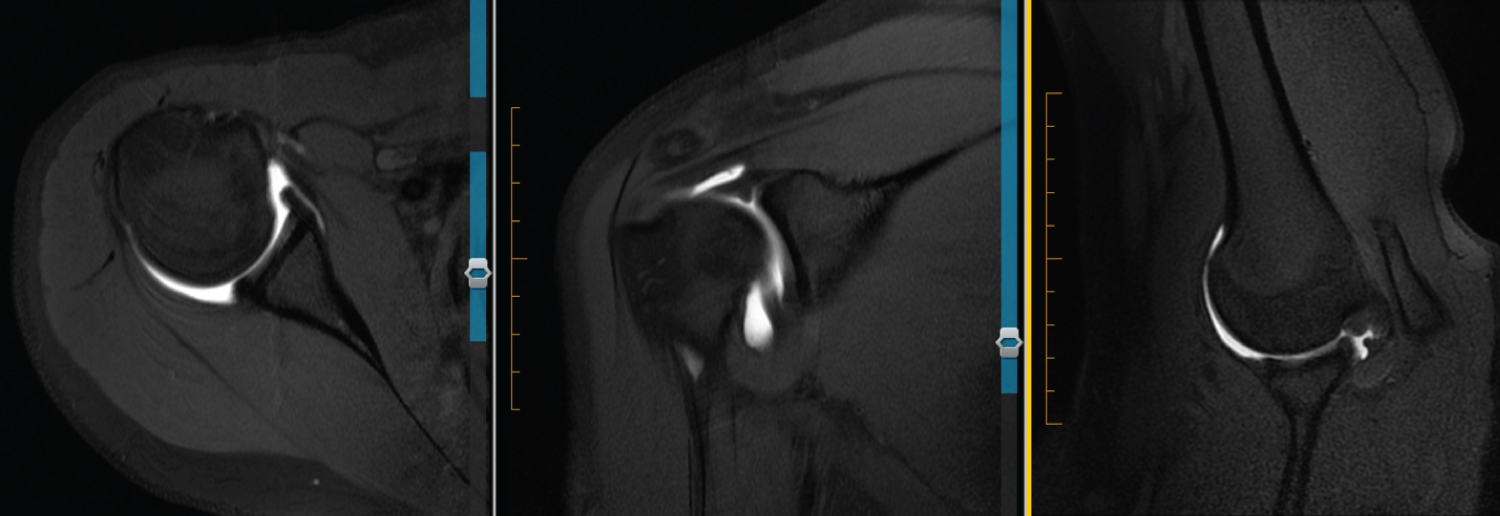

Figure 8: 17 M L MRA. Axial view shows rounding and blunting of labrum with undefined features. ABER looks normal. View Figure 8

Figure 9: 15 F R MRA. Axial view shows blunted anteroinferior labrum with IGHL adjacent to it. Seems a little more defined compared with others. NO ABER views. View Figure 9

Figure 10: 28 F R MRA. Axial view shows blunting of anteroinferior labrum compared with posterior triangular appearance. ABER view appears normal. Also appears to be anterosuperior labral tear on coronal. View Figure 10